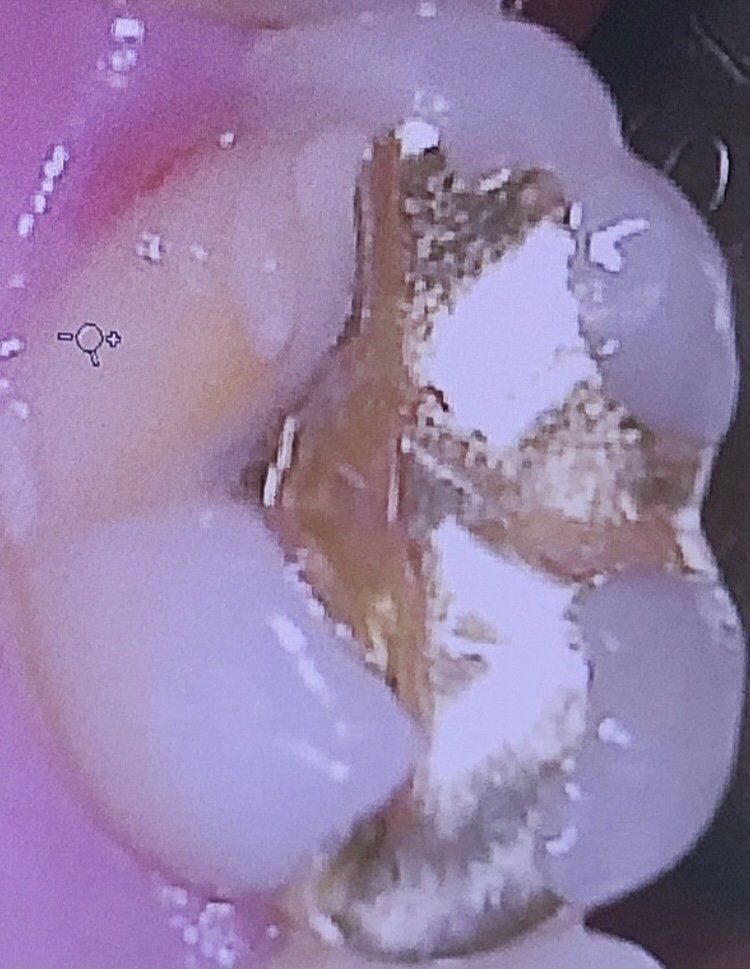

인레이한 어금니 치아파절 신경치료 필수인가요?

오래전에 인레이한 어금니 치아가 파절되었습니다 보시다싶이 많이 파절되어있는데 한달이 넘게 방치되어있긴 합니다 좀 불편한건 많이 날카롭다는정도..? 한달이 넘긴 했지만 아직까지 시리거나 아픈 통증이나 별다른 불편함이 없습니다 병원에서 신경치료 한 후 크라운을 하자고 하는데 크라운은 해야되는게 맞지만 아프지 않아도 이 정도 파절이면 신경치료를 꼭 해야하고 크라운을 해야하는건가요?

• 1번 째 사진

사진으로 보이는 파절이면 교두1개가 파절된것인데 파절정도가 적지 않습니다.

또한, 기존의 인레이 크기도 큰 편이라, 크라운은 불가피해 보입니다.

다만, 신경치료를 해야할지는 엑스레이를 보아야 어느정도 판단이 가능합니다.

신경이 큰 경우에는 크라운을 위한 치아삭제시 신경과의 거리가 가까워져서 지금당장 통증이 없어도 신경치료가 필요하다고 판단될 수 있습니다.